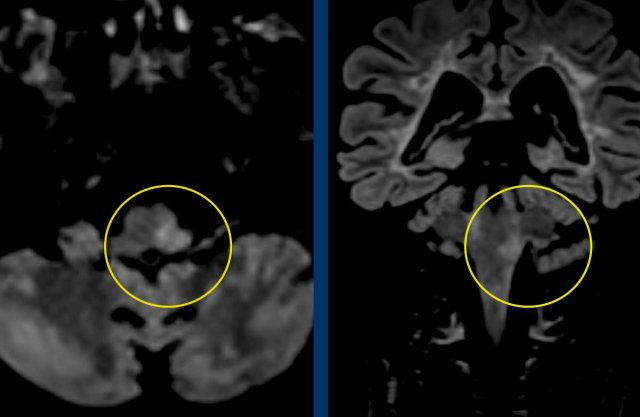

Case

45 year-old man with sudden onset Horner syndrome, dysphagia, ipsilateral ataxia, nystagmus and sensory impairment ipsilateral face and contralateral body.

Images

Diffusion weighted images DWI (B1000) and ADC images show restricted diffusion in the medulla oblongata on right side due to a lateral medullary infarction.

Continue with the MRA of the neck...

Contrast enhanced MRA of the neck (on the right) shows narrowing of the right vertebral artery .

The T1WFS-image of the neck shows a  hyperintense crescent signal intensity in the wall of the right vertebral artery typical of an intramural hematoma.

Conclusion

Dissection of the right vertebral artery resulting in a medullary infarction.